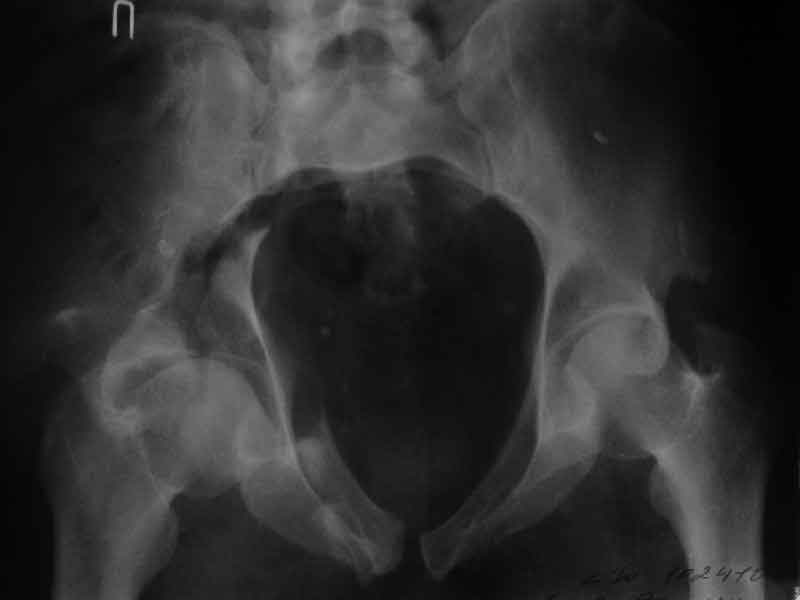

Дополнение, минимальный набор необходимых прекций, необходимых для лечения повреждений вертлужной впадины

Фас. Inlet